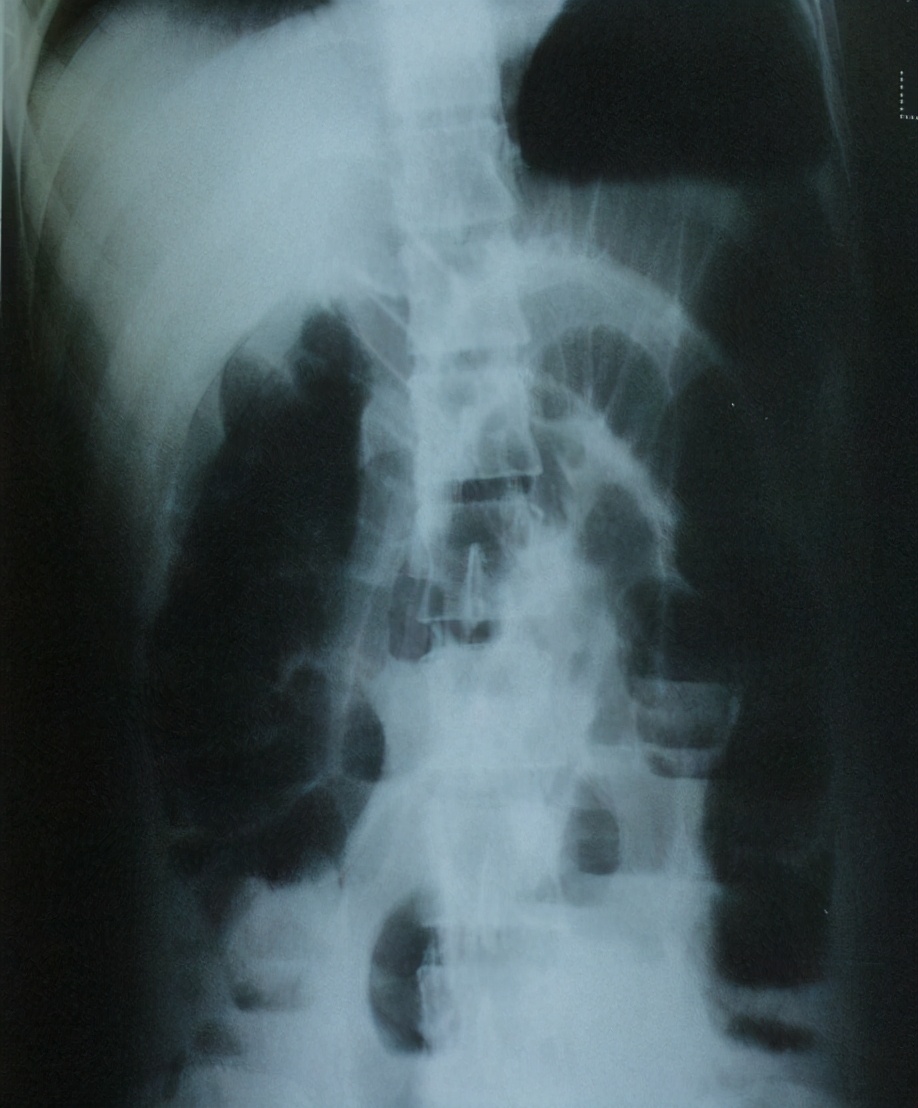

(1)立位或卧位腹平片: 肠梗阻4-6小时后即可检出肠袢胀气,表现为多个阶梯状气液平面;空肠粘膜的环状皱壁呈“鱼骨刺”样;绞窄性肠梗阻可见孤立、突出、胀大肠袢。 注意:X线阴性不能排除肠梗阻。怀疑肠套叠,肠扭转或结直肠癌时作钡灌肠。

空肠梗阻“鱼骨刺”样改变